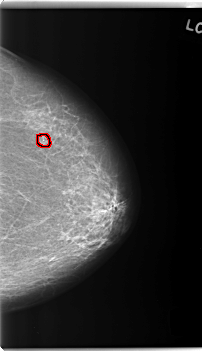

FILE: C_0231_1.RIGHT_CC.OVERLAY

TOTAL_ABNORMALITIES 1

ABNORMALITY 1

LESION_TYPE MASS SHAPE OVAL MARGINS ILL_DEFINED

ASSESSMENT 5

SUBTLETY 5

PATHOLOGY MALIGNANT

TOTAL_OUTLINES 1

BOUNDARY